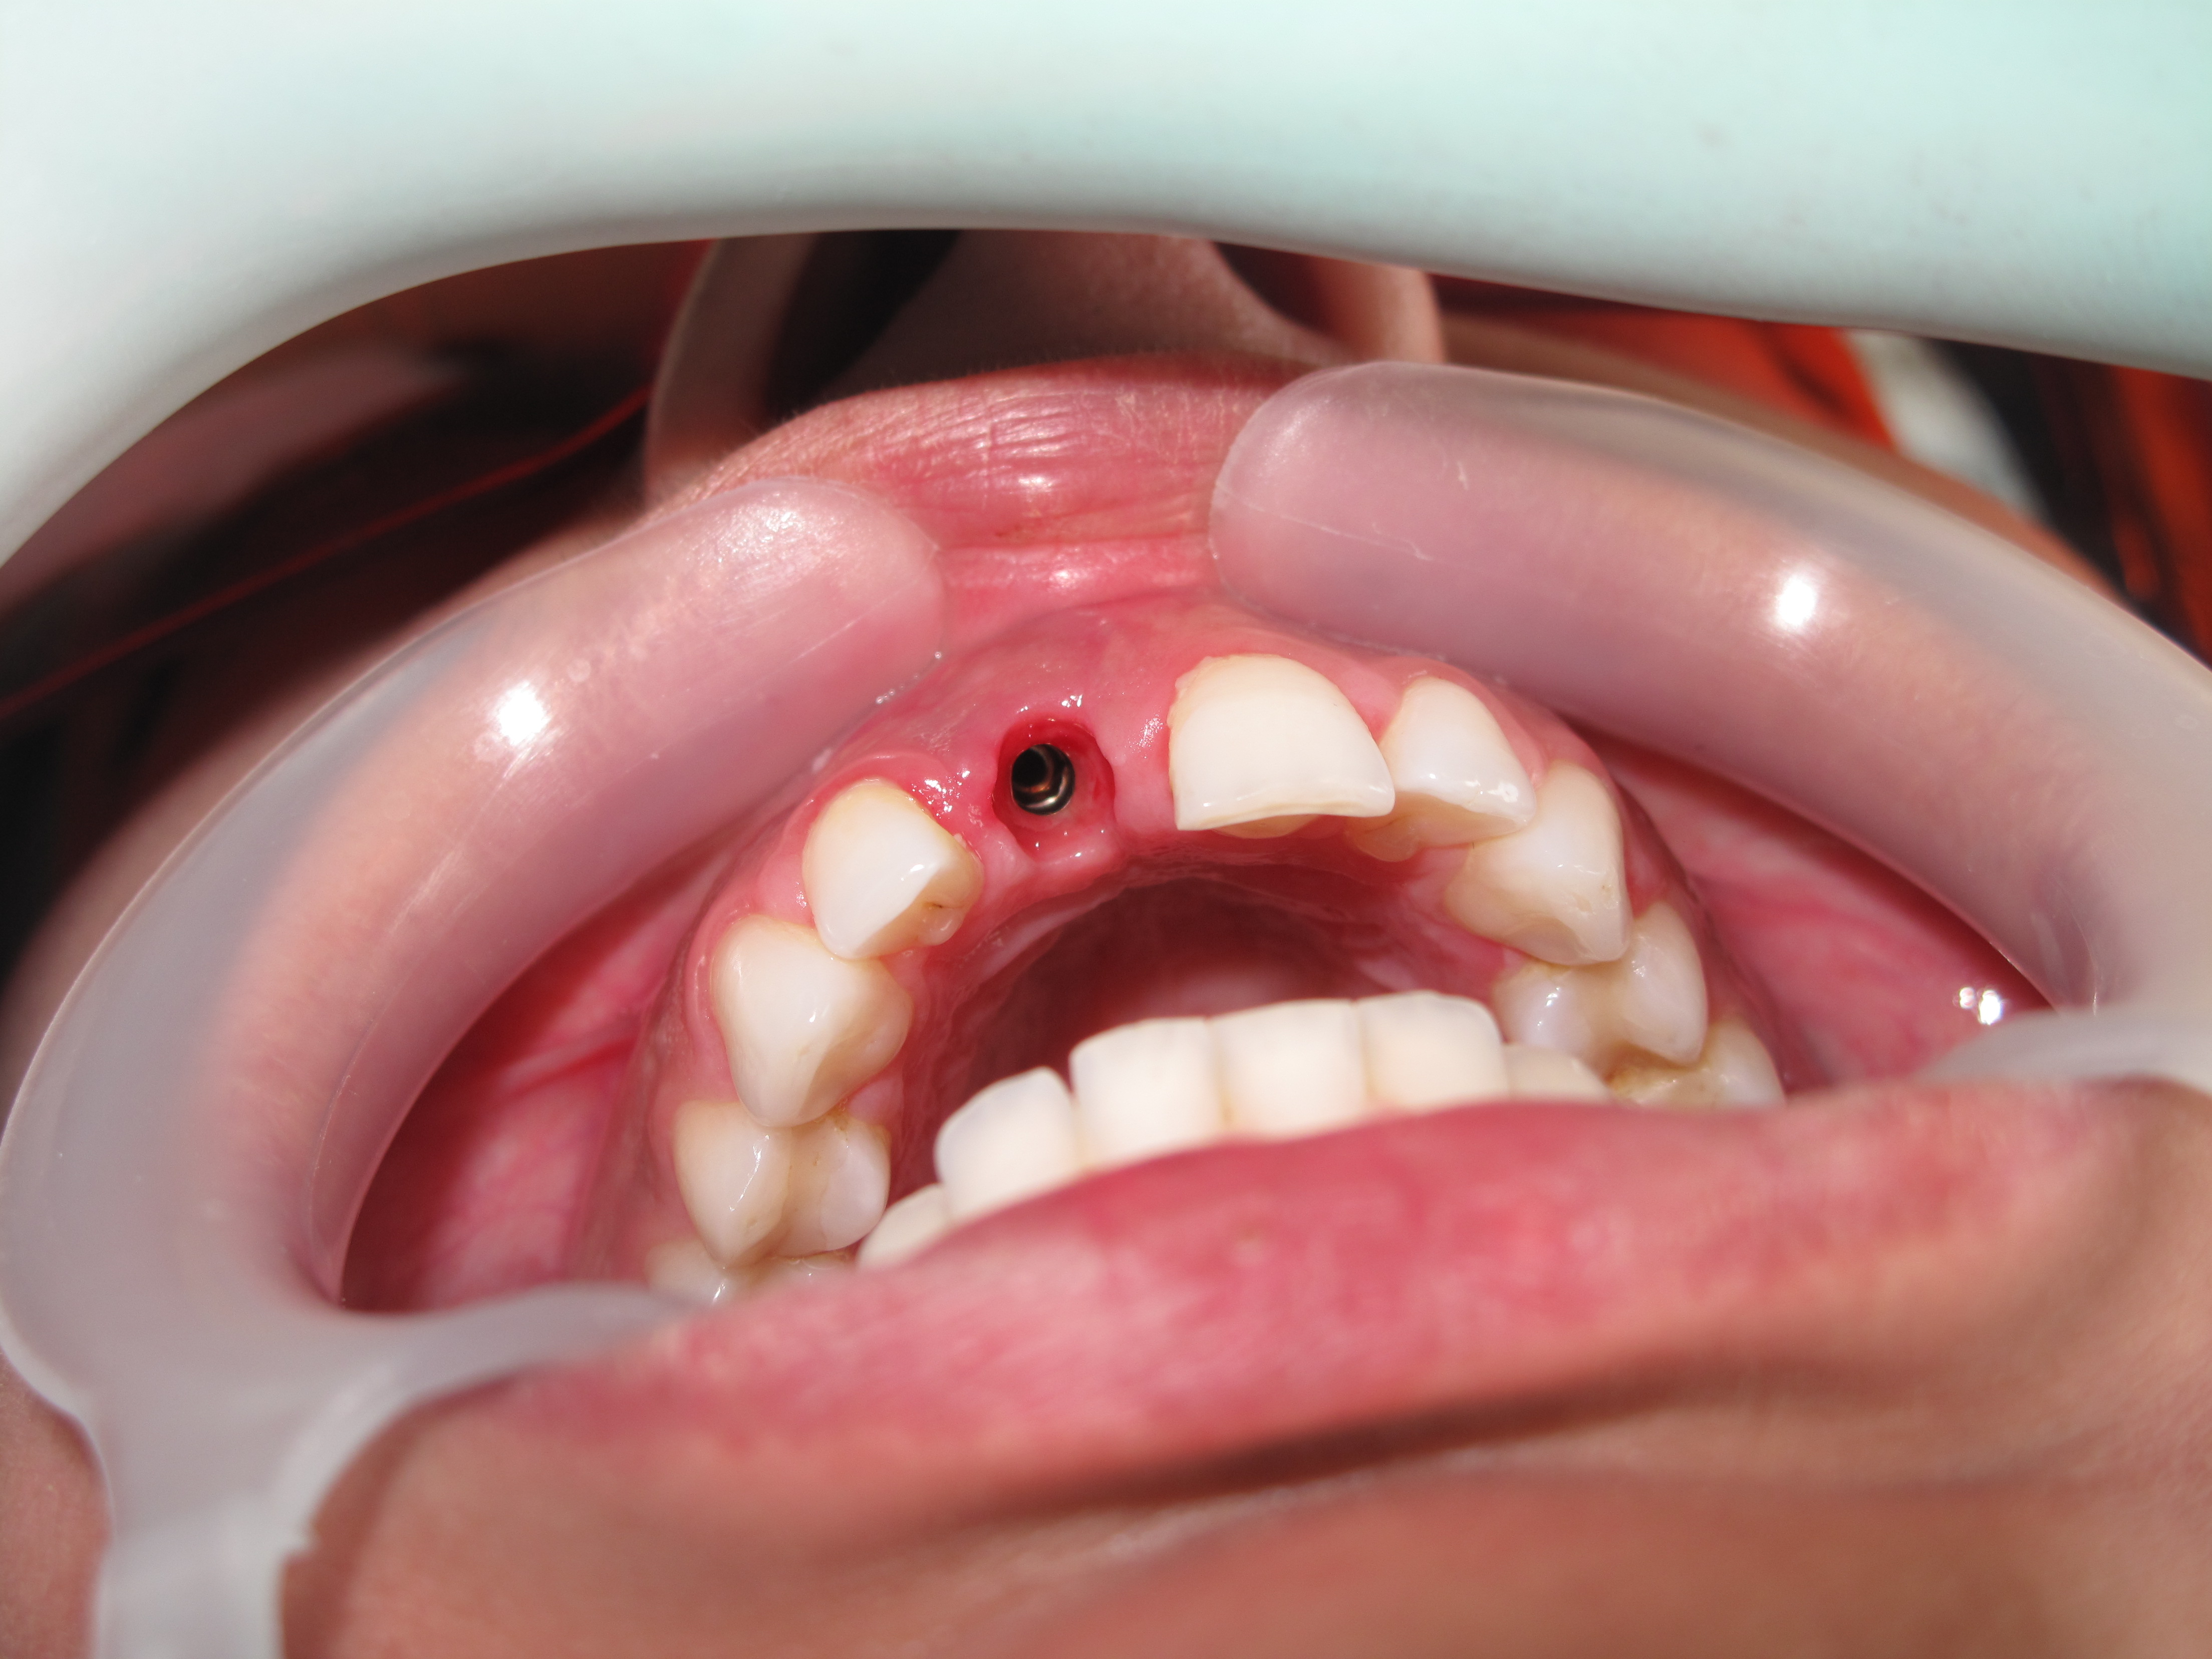

Dental implants surgery should always be performed by Oral surgery or dental surgeon specialist, also called periodontist and oral surgeon to minimize the risks of this very accurate procedure.

Dental implants are most difficult in the esthetic zone especially when it needs Bone graft management.